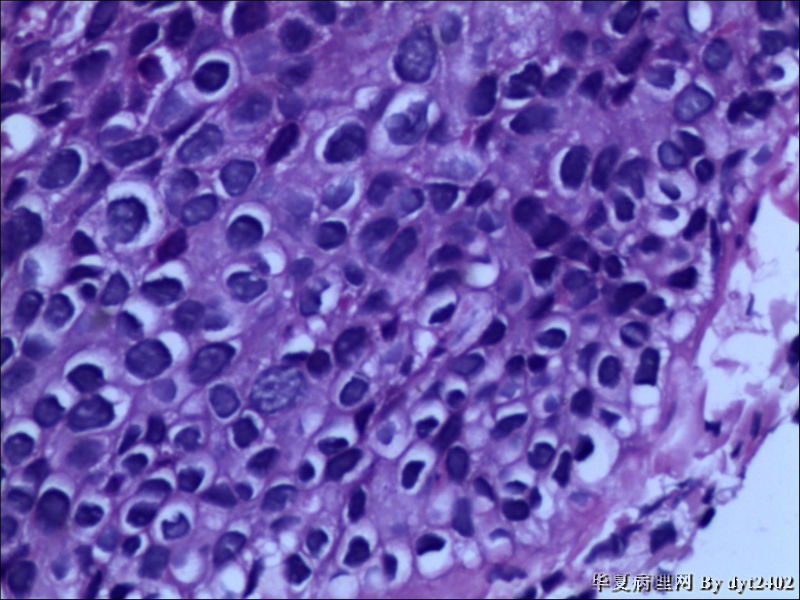

这样的外阴病变 发个原位癌是否合适?

• 这样的外阴病变 发个原位癌是否合适?图2

图2

原位癌够了,不排除其他地方有浸润。

似乎有浸润了

VIN III,做个银染或者标个免疫组化看一下基底膜是否完整。

VIN III